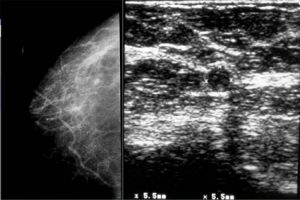

Diplomados en Ultrasonografía